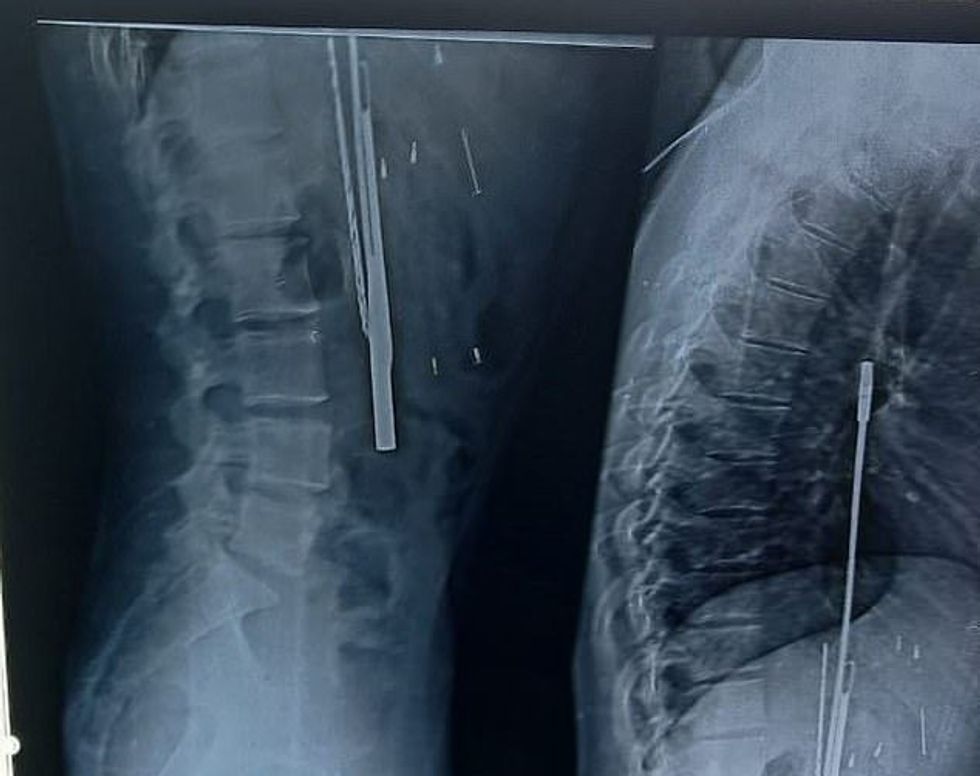

E ëma e tij, Kusma Thakur, u tha mjekëve se djali i saj "hante gjithçka që i dilte përpara", dhe kështu ata u detyruan t'i bëjnë rëntgenografinë për të konstatuar se për çfarë bëhej fjalë.

Mirëpo, mbetën të habitur kur në bark i gjetën thika, kaçavidë, bisturi dhe objekte tjera. E dy ditë pas intervenimit kirurgjik, mjekët kanë publikuar listën e plotë të objekteve që i kanë gjetur në barkun e fermerit indian që tani po rimerr veten në spitalin e psikiatrisë. /Telegrafi/